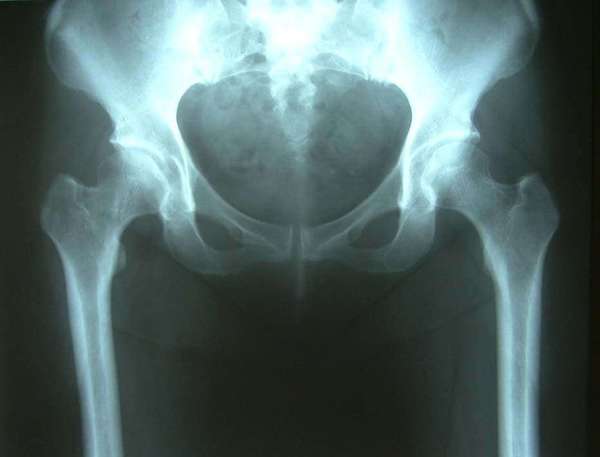

术前髋臼对股骨头的包容与覆盖不足